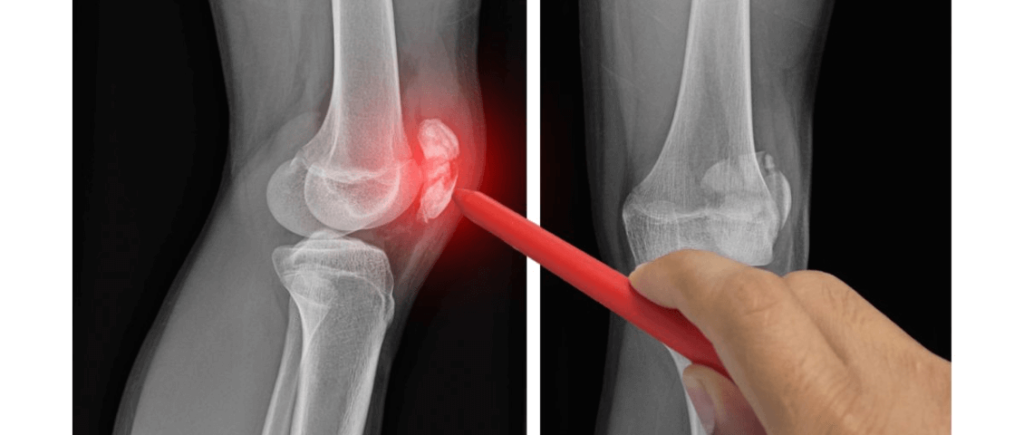

¿Por qué duelen las rodillas?

El dolor de rodilla es una queja frecuente que puede afectar a personas de todas las edades. Las causas del dolor de rodilla pueden variar considerablemente, pero a continuación se presentan algunas de las más comunes:

Lesión de rodilla:

Una de las causas más comunes del dolor de rodilla es la lesión. Esto puede incluir esguinces, desgarros de ligamentos, meniscos rotos y fracturas. Las lesiones suelen ocurrir durante actividades físicas, deportes o debido a accidentes.

Artritis:

La artritis, en sus diversas formas, es una causa principal de dolor de rodilla, especialmente en personas mayores. La osteoartritis es la más común, caracterizada por el desgaste del cartílago en la articulación de la rodilla.